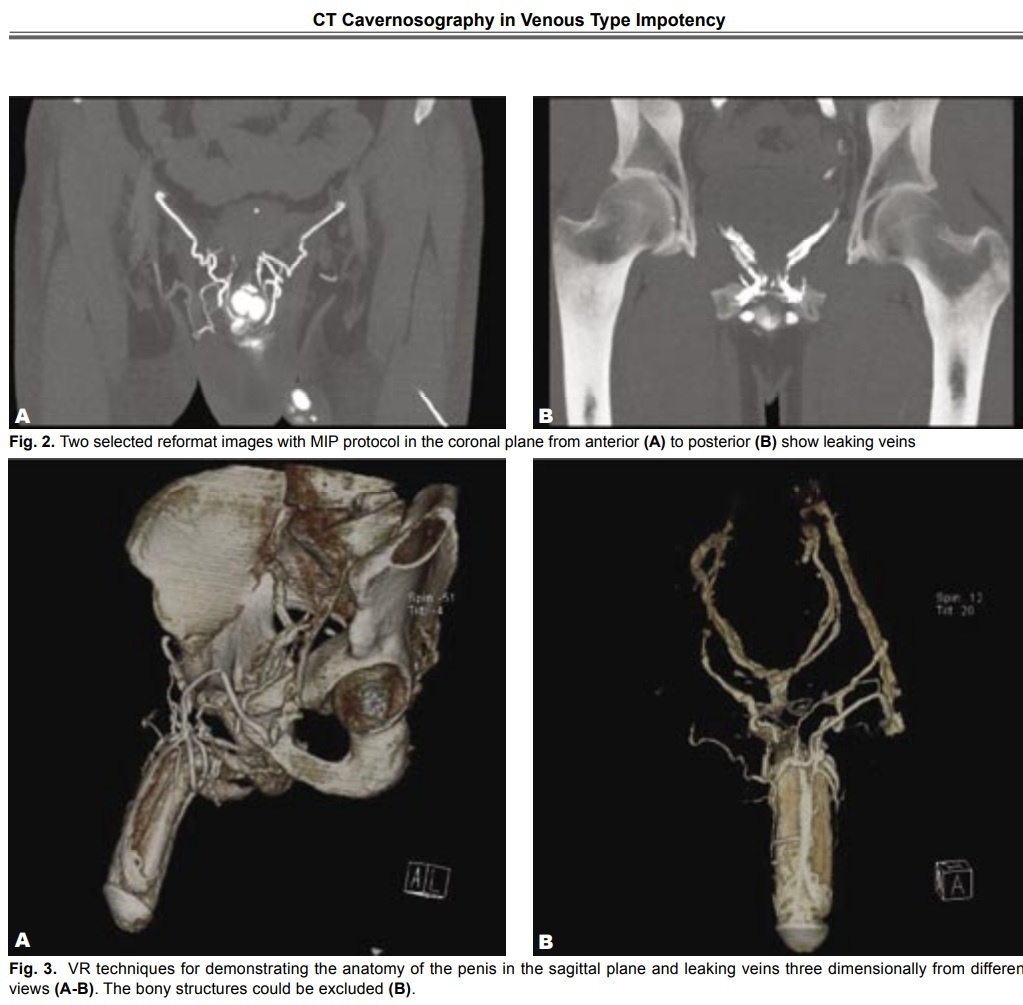

Кавернозография — это поиск «дырок» с помощью контраста (безопасная «краска» для крови); компьютерного томографа (чтобы увидеть, куда «утекает» краска).

Производится сканирование в компьютерном томографе по определенному алгоритму 5–7 минут.

Результат - 3D-карта «утечек» на компьютере.

Диагноз: Венозная утечка через глубокую дорсальную вену (тип «B» по классификации).